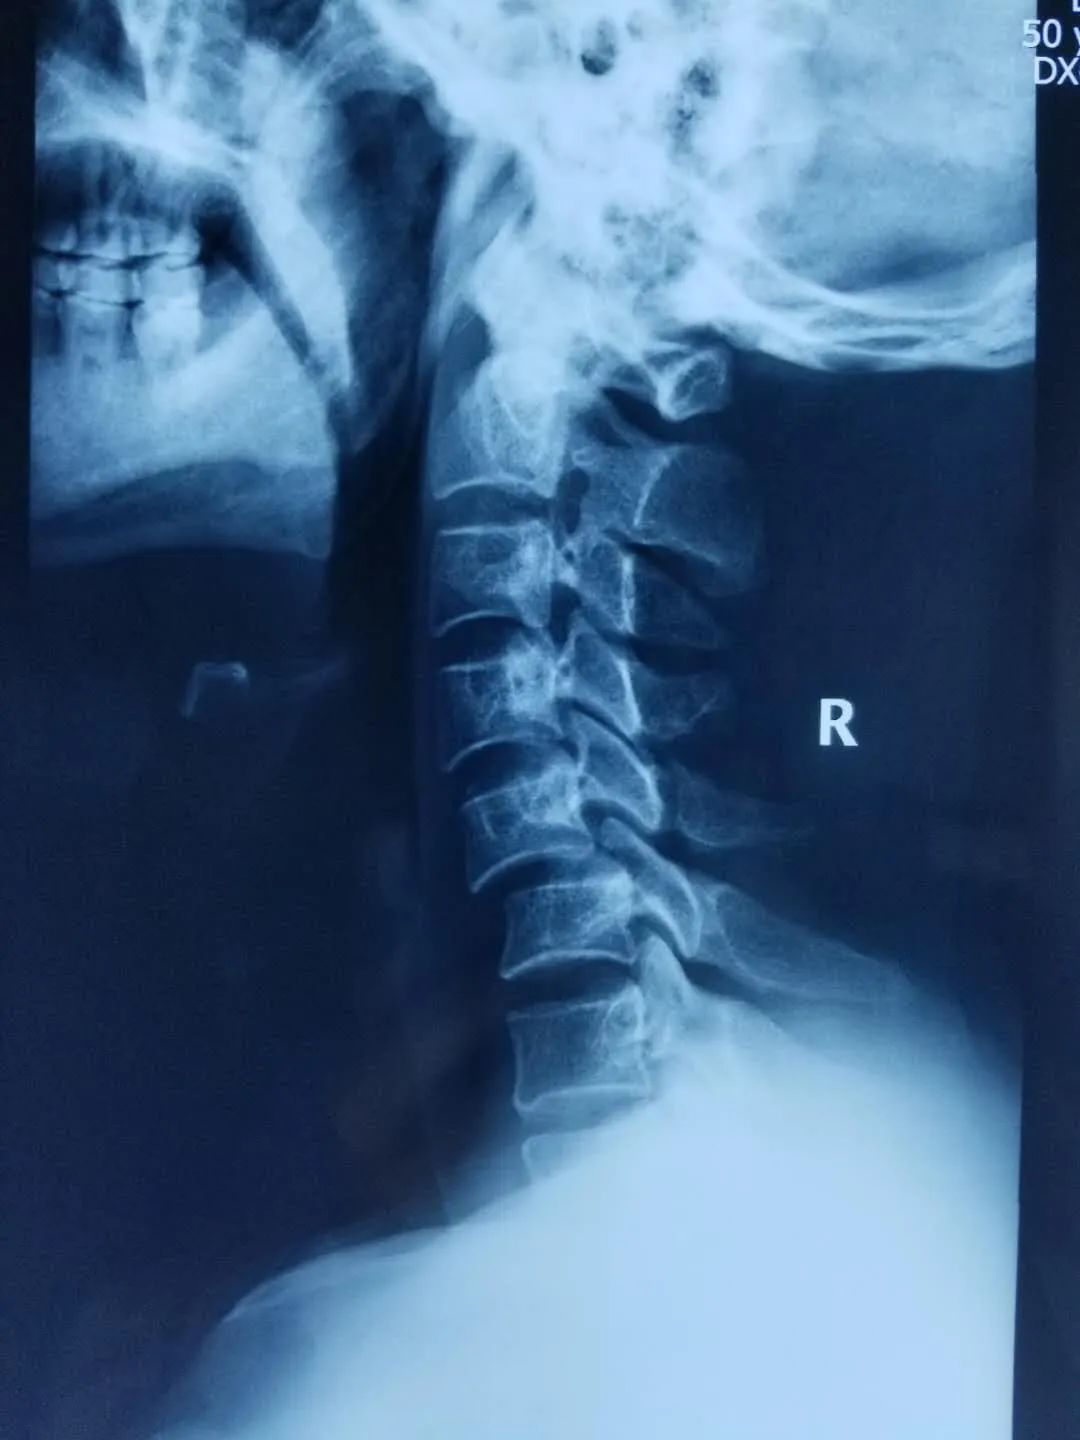

四个多月来,患者根据医生建议一直佩戴颈托休养,但佩戴颈托给患者的生活带来了很大的不便,吃饭困难,睡觉困难,庄稼地里的农活也是被一天天的耽搁。4个月后,患者去当地医院复查,可是带给他们的依旧是不好的消息。复查CT显示:C5椎体前滑脱(Ⅱ°),椎小关节脱位,导致椎管及椎间孔狭窄。椎体滑脱比之前更严重了,而且病人也感觉到手指麻木的症状加重了,并且右胳膊酸困疼痛,当地医院的医生建议患者尽快到大医院治疗,否则会有瘫痪的危险。

患者家属经过多方打听后找到了甘肃省中医院骨肿瘤科李红专主任,李红专给患者详细查体、阅读影像学资料后认为患者颈椎滑脱很容易造成截瘫,伤后4个月滑脱进一步加重,说明颈椎不稳定,患者没有瘫痪已属幸运,如果继续保守治疗,给予头-颈-胸支具固定,一方面防止滑脱再次加重引起患者截瘫,另一方面会给患者生活带来很大不便,严重影响患者生活质量。但如果进行手术治疗,患者已摔伤4个多月,伤处瘢痕粘连严重,滑脱复位困难,单纯前路或后路或前后路联合都可能无法使滑脱复位,且稍有不慎就会损伤到脊髓,导致病人截瘫。

通过仔细查体、阅片、查阅文献资料,李红专团队决定为患者进行手术治疗,5月8日为患者实施颈椎滑脱前-后-前路松解复位前路椎间融合后路钉棒系统固定手术,手术历时6小时,术后患者恢复良好,临床症状消失,四肢感觉、运动功能正常,现患者已经治愈出院,随访患者恢复良好。